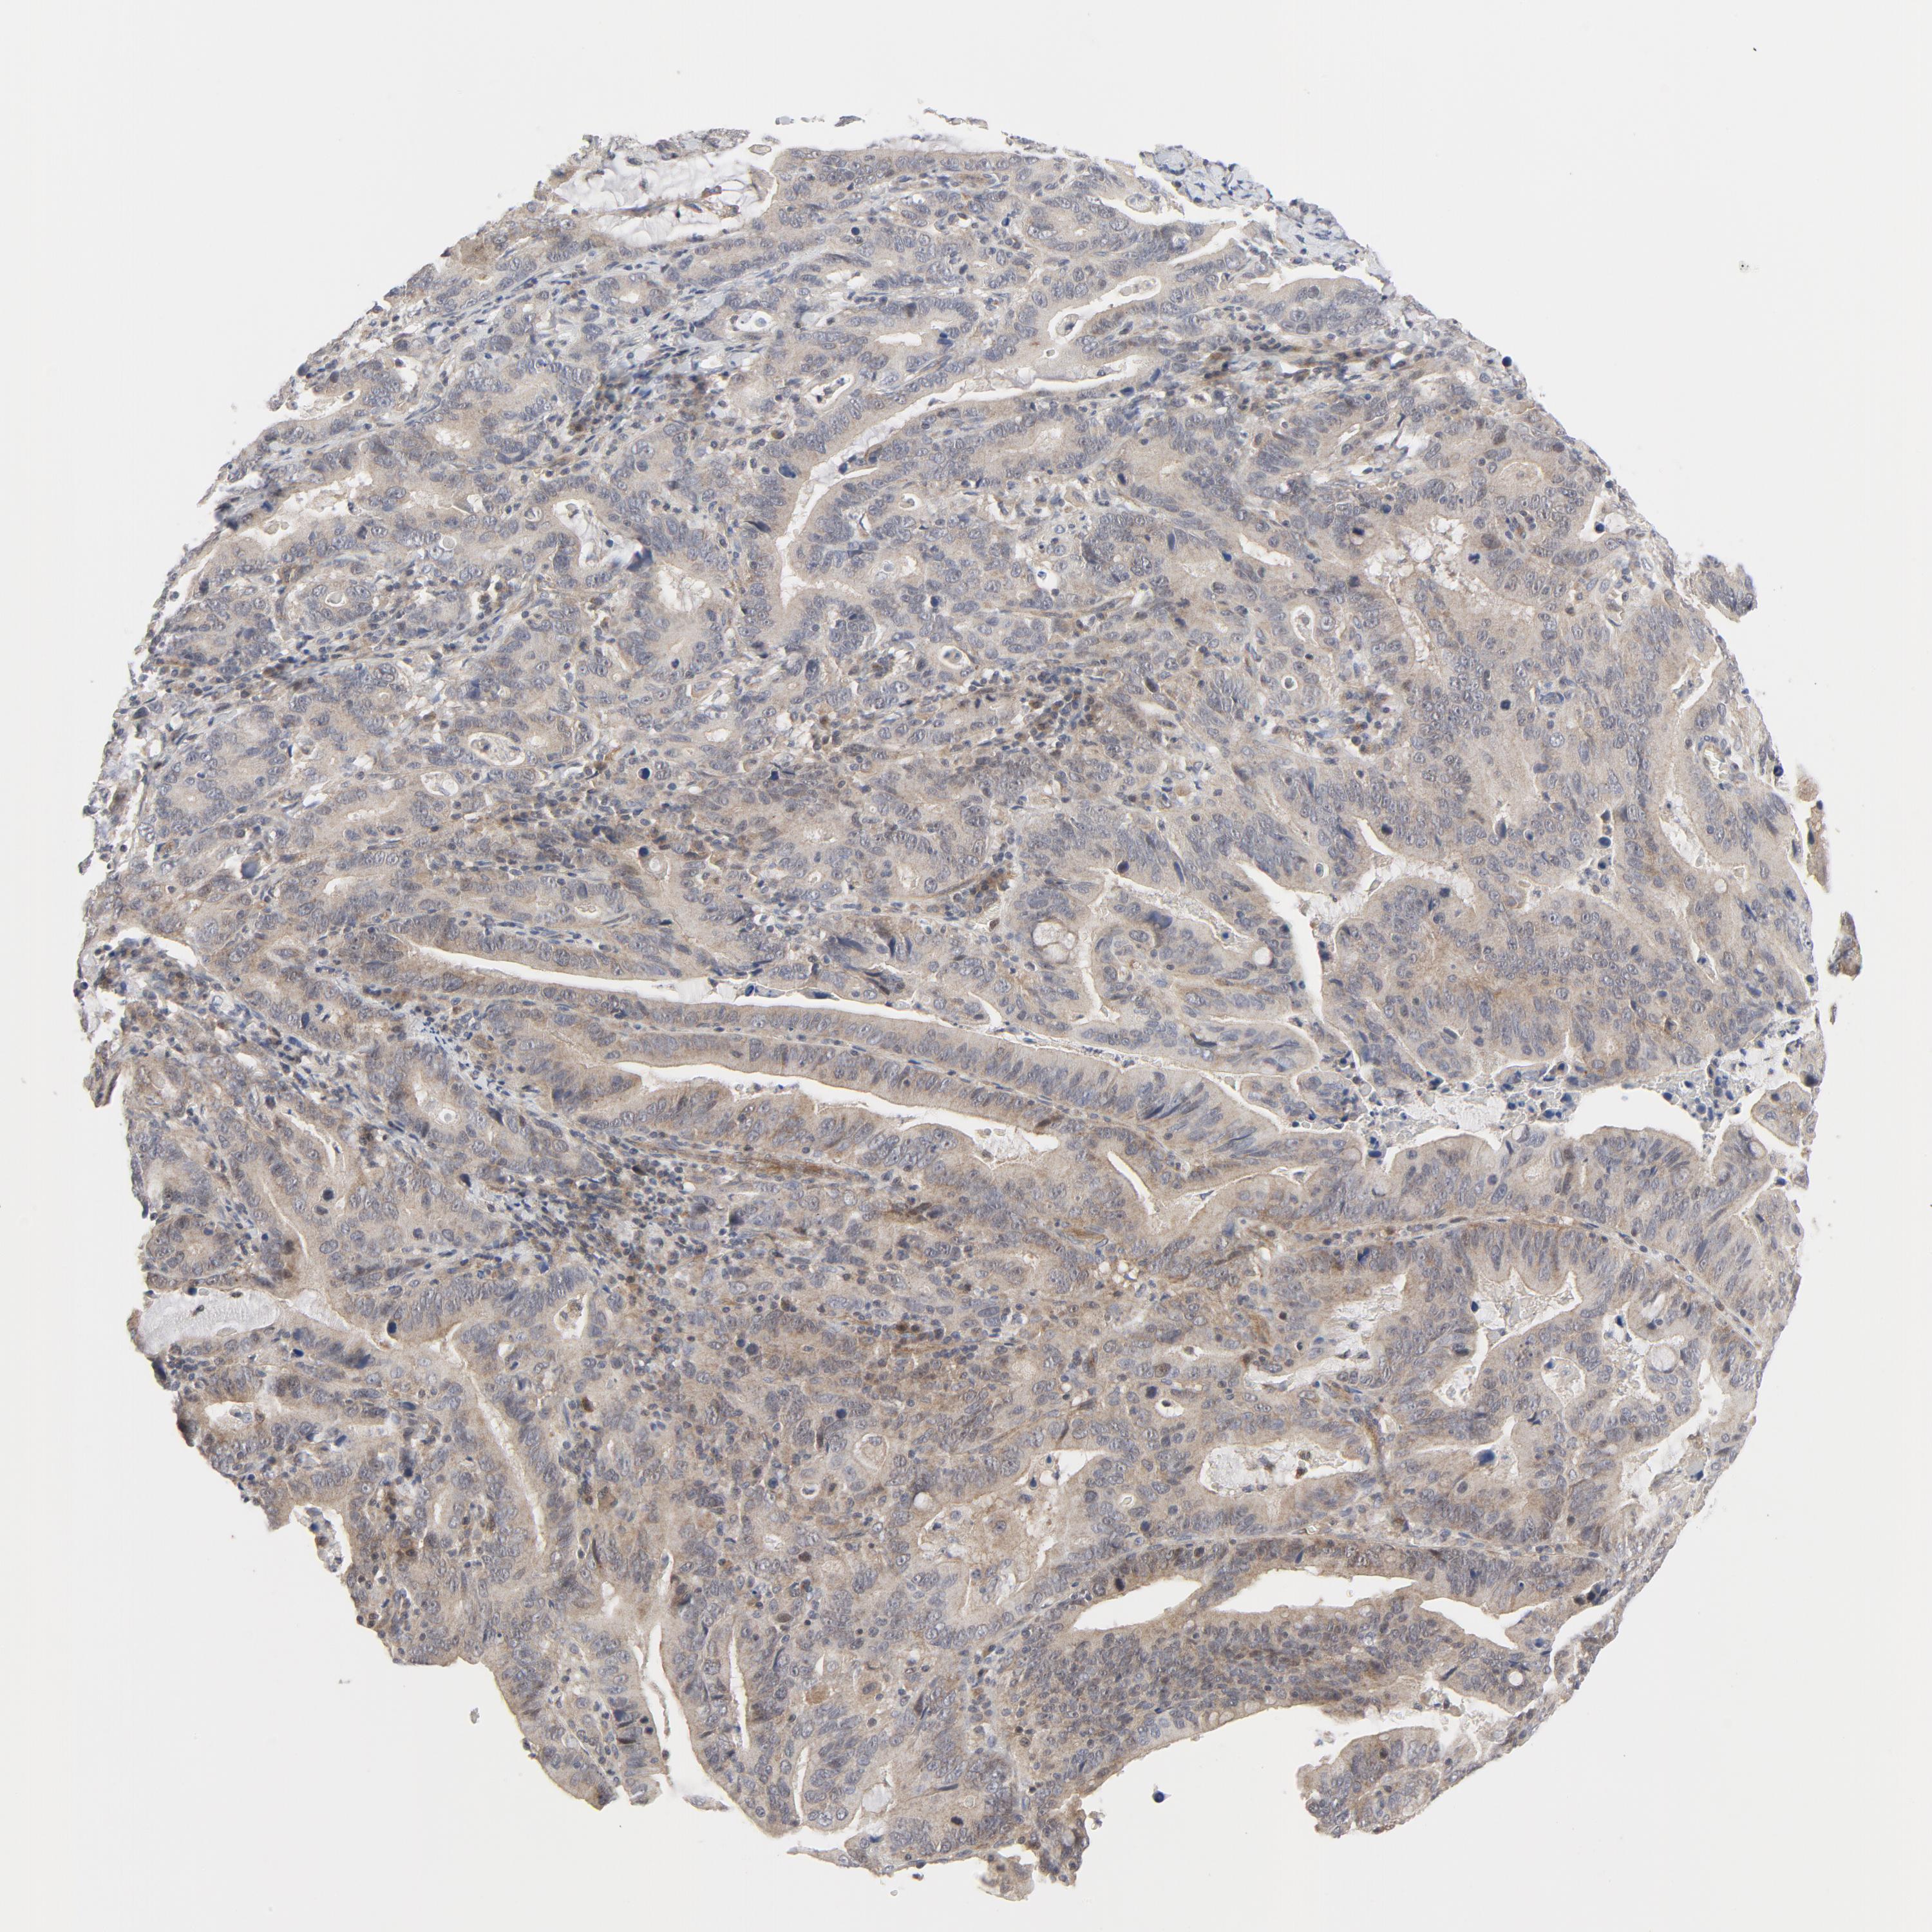

STOMACH CANCER - Protein expressioni

A mouse-over function shows sample information and annotation data. Click on an image to view it in a full screen mode. Samples can be filtered based on level of antibody staining by selecting one or several of the following categories: high, medium, low and not detected. The assay and annotation is described here.

Note that samples used for immunohistochemistry by the Human Protein Atlas do not correspond to samples in the TCGA dataset.

Antibody stainingi

Antibody staining in the annotated cell types in the current human tissue is reported as not detected, low, medium, or high, based on conventional immunohistochemistry profiling in selected tissues. This score is based on the combination of the staining intensity and fraction of stained cells.

Each image is clickable and will lead to virtual microscopy that enables deeper exploration of all samples and also displays staining intensity scores, fraction scores and subcellular localization as well as patient and tissue information for each sample.

Antibody HPA001633

Antibody CAB004262

Staining

High

Medium

Low

Not detected

Intensity

Strong

Moderate

Weak

Negative

Quantity

>75%

75%-25%

<25%

None

Location

Nuclear

Cytoplasmic/membranous

Cytoplasmic/membranous,nuclear

Adenocarcinoma, NOS

Adenocarcinoma, High grade